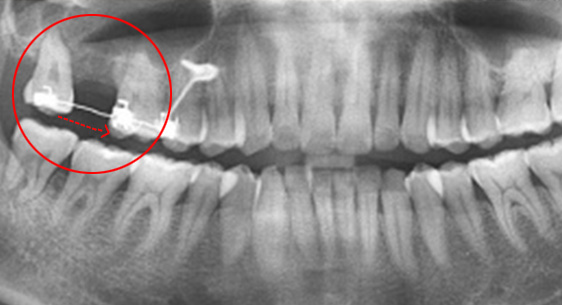

심한 염증으로 치조골이 광범위하게 소실, 아래쪽 신경관이 가까이 있어 치근단수술이 불가능한 상태, 타 병원에서 임플란트 진단을 받았지만, 고운미소치과에서 치아를 발치하고 뿌리 쪽 염증을 제거한 후 발치한 치아를 다시 심는 치아재식술을 시행하였습니다.

기존 신경치료 부위에 염증과 치조골이 소실되고 있는 상태

치아를 발치하고 염증을 제거, MTA로 충전하고 치아를 다시 심음.

(난이도 최상)